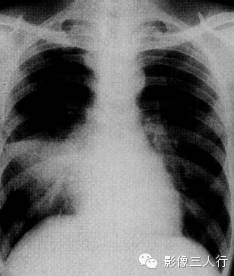

报告示范:右肺中下肺野可见大片密度增高影,上缘清晰,右心缘模糊。侧位片示病变位于右中叶。胸廓对称,气管纵隔居中。心脏大小、形态、位置正常。双侧膈肌光滑,肋膈角锐利(图1)。

图1右中叶大叶性肺炎

(A)正位